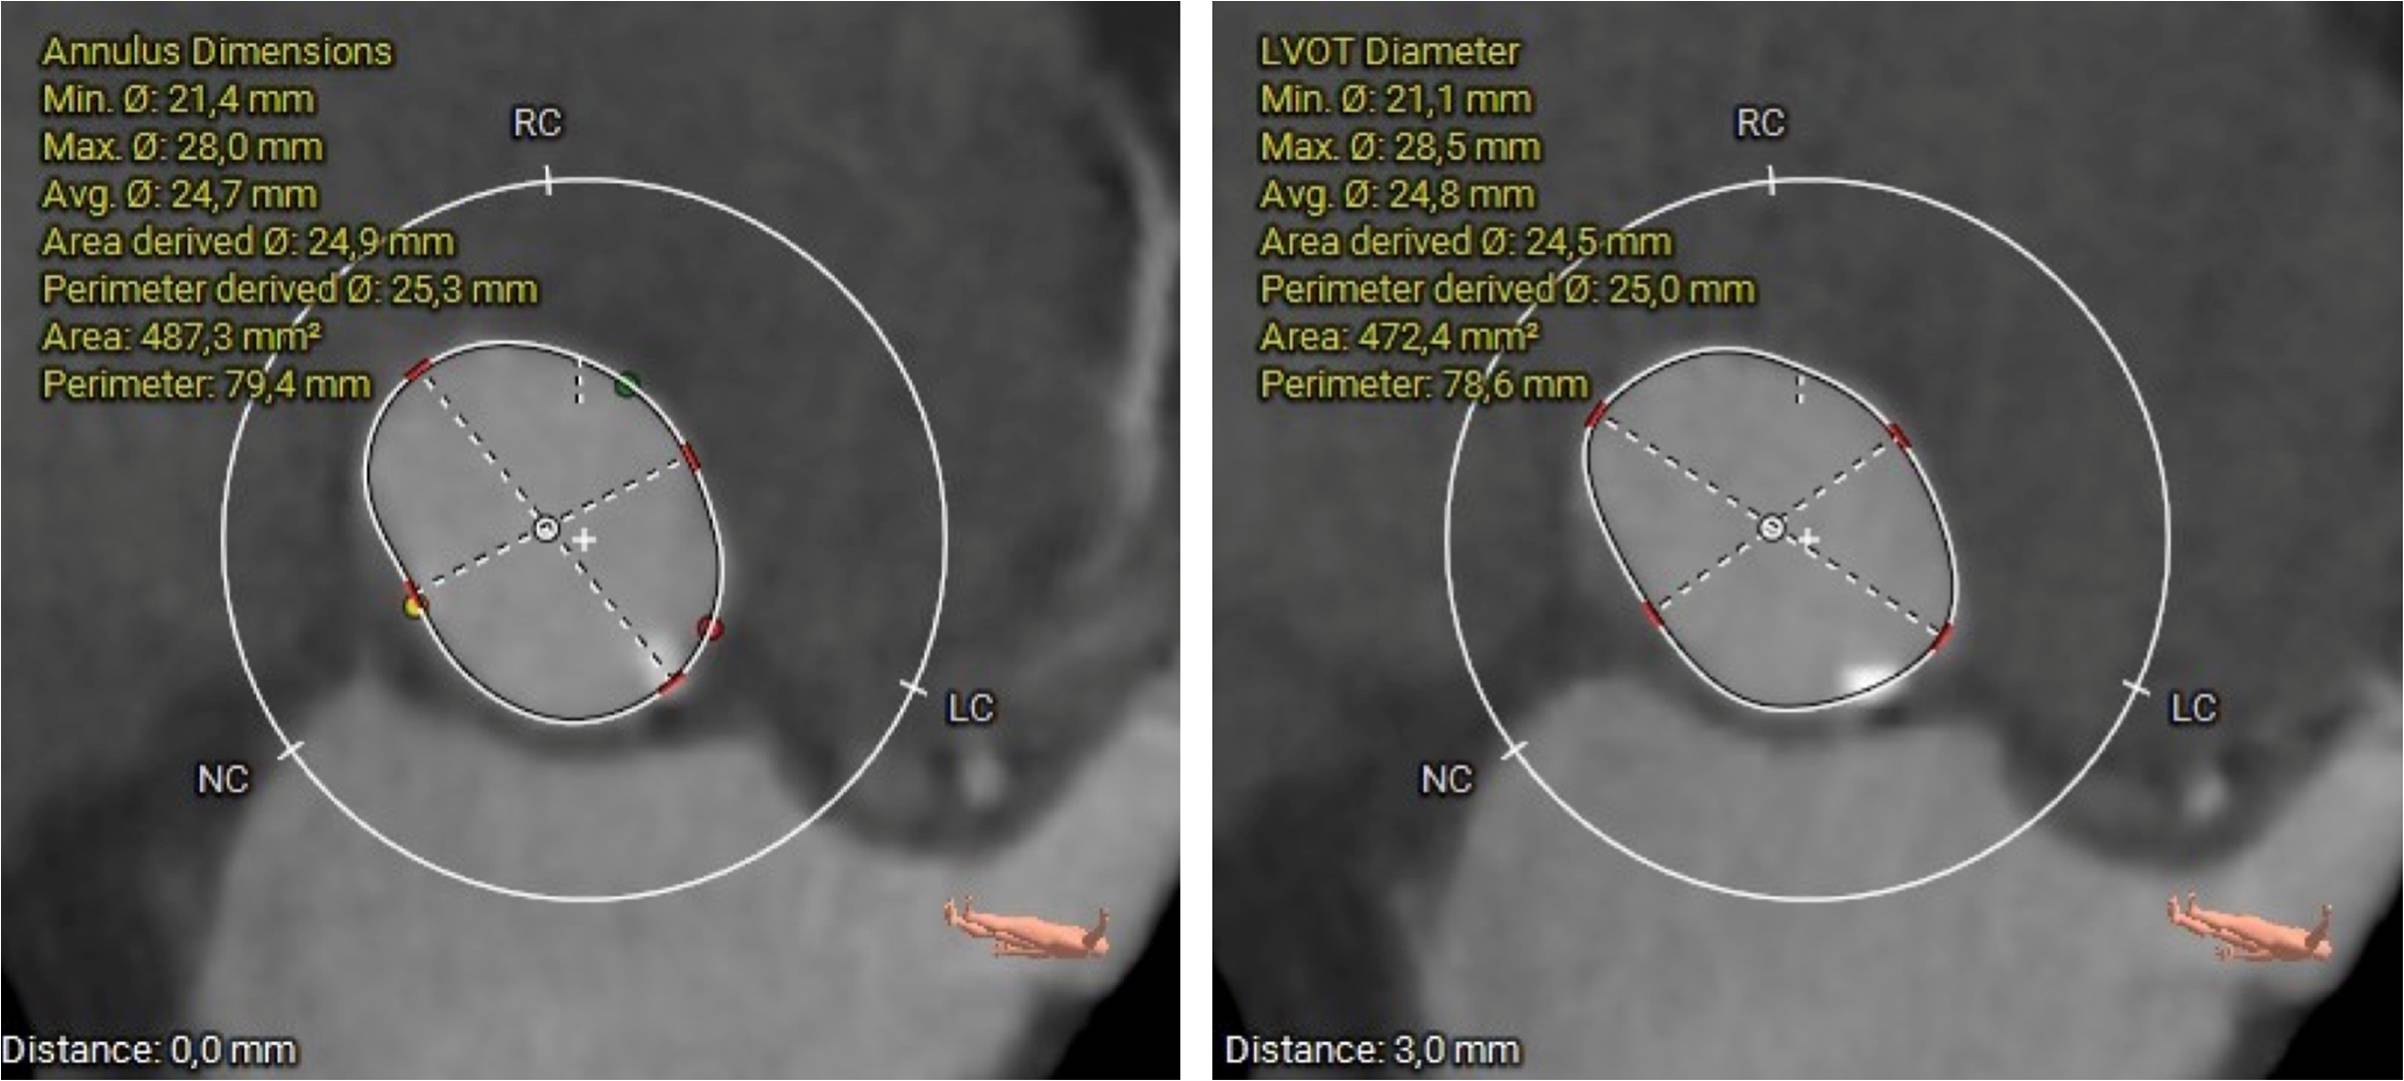

A super-rigid guidewire was inserted into the left ventricular cavity, and a valvulotomy was performed using a 23x40mm balloon catheter. After this, a successful implantation of a Portico 29mm aortic prosthesis was performed. During suturing of the access site, the patient developed persistent hypotension and bradycardia. A decision was made to perform catheterization of the left coronary artery trunk. During the angiogram, compression of the left coronary artery trunk by a hematoma in the projection of the fibrous ring was revealed. A decision was made to perform stenting of the left coronary artery trunk. The stent was successfully implanted in the left coronary artery trunk. Hemodynamics were restored. The patient was discharged on the 4th day after TAVI. A control MSCT was performed several months later.